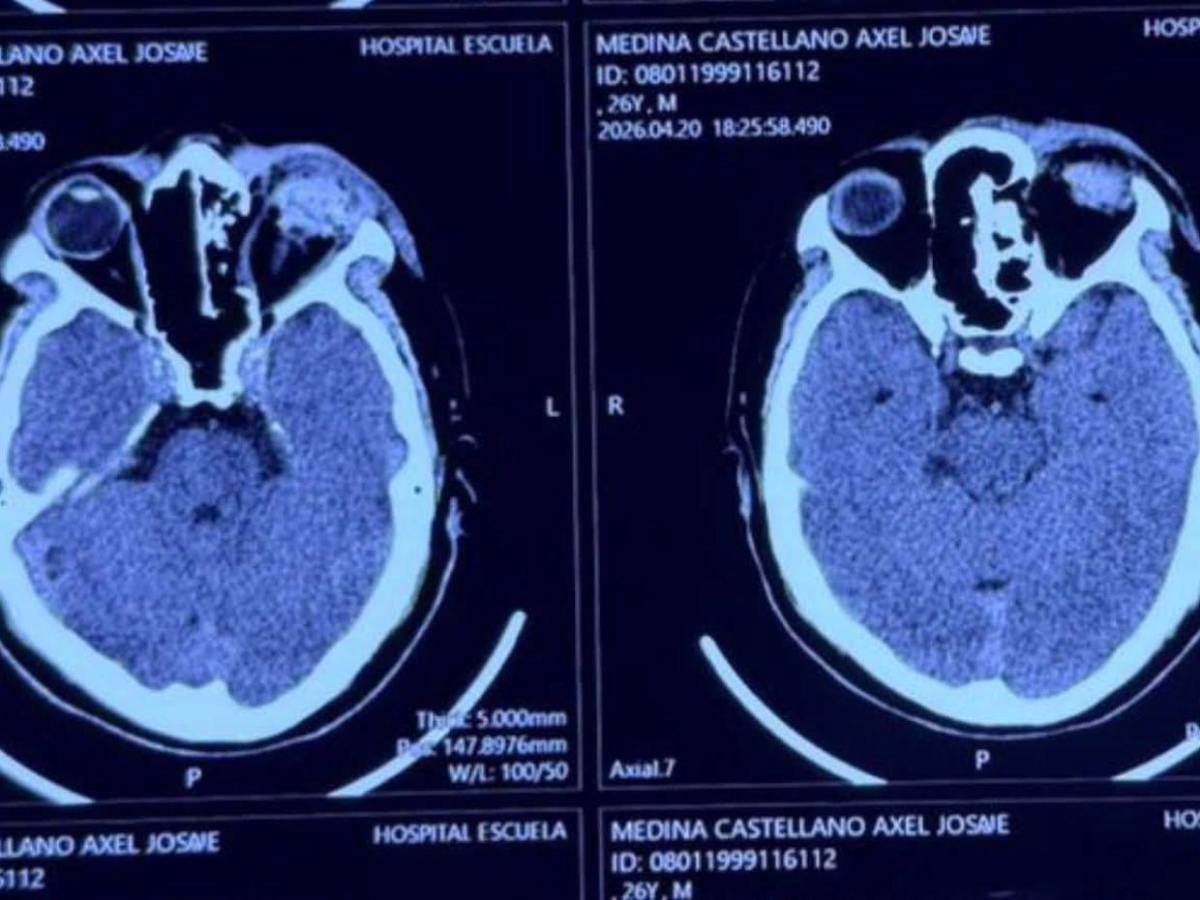

El joven que perdió su ojo izquierdo fue identificado como Axel Josué Medina, estudiante de la máxima casa de estudios que figura como presidente de Trabajo Social.

Tras el impacto, el joven fue trasladado de emergencia hacia el Hospital Escuela, donde presuntamente habría sido "sometido a una enucleación" (extirpación del globo ocular).